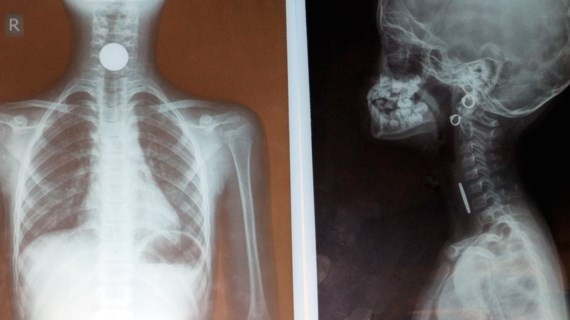

X光片顯示,食道內有一枚類似硬幣的金屬異物卡住。

成功為女童取出食道內硬幣 ảnh 1 直徑約2.3厘米的硬幣被取出。

在醫院裡,經診探、各類檢驗及頸部X光照後,醫生發現在病人的頸部裡面有一個強烈反射硬幣狀異物。耳鼻喉科隨即將病童轉至麻醉加護科以進行內窺鏡手術。最後醫生們已成功從女童食道取出一枚直徑2.3釐米的硬幣◆